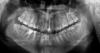

Force Опубликовано 13 октября, 2012 Поделиться Опубликовано 13 октября, 2012 Согласен. Если вы носили брекеты, то далеко не факт, что у вас хорошая окклюзия. А судя по снимку, совсем наоборот Ссылка на комментарий

Force Опубликовано 14 октября, 2012 Поделиться Опубликовано 14 октября, 2012 Поблема очевидна. Стираемость, клиновидные, избыточные наклоны передних зубов- все факторы, характерные для дисфункциональных состояний. Необходима функциональная диагностика и два варианта: либо шина, либо полная реконструкция вашего прикуса, но теперь не только с учетом зубов, но и сустава, мышц и всей краниомандибулярной системы.Ваша система самодеструктивна. Ссылка на комментарий